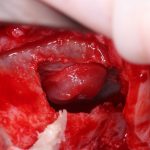

Создание доступа в субантральную полость.

Существует несколько способов создания доступа в субантральную полость (хотя, на самом деле, в полость верхнечелюстную, ибо субантральную нужно еще смоделировать). Некоторые (и мы, иногда тоже) используют для этого алмазные шаровидные боры:

Я же в своей практике для создания доступа использую ультразвук, а именно — электрический пьезохирургический аппарат VarioSurg (NSK). Он позволяет делать очень красивый и практичный доступ любой формы:

Как создаётся доступ?

Доступ в субантральную полость — наше всё. Форма и положение его апертуры — это то, от чего будет зависеть весь дальнейший ход операции и вероятность возникновения интраоперационных проблем. И сейчас я расскажу вам о некоторых нюансах создания правильного доступа, вне зависимости от того, чем и как вы его делаете.

Одна из самых распространенных ошибок — это высокое положение апертуры. Откуда это пошло, ума не приложу. В результате, от нижнего края апертуры до дна субантральной полости остаётся с десяток миллиметров, а это снижает возможности манипуляций и контроля за этой областью:

Выход простой: Делайте нижний край апертуры доступа как можно ниже. В идеале — почти впритык ко дну гайморовой пазухи. И вы удивитесь, насколько проще станет делать синуслифтинг при таком подходе: